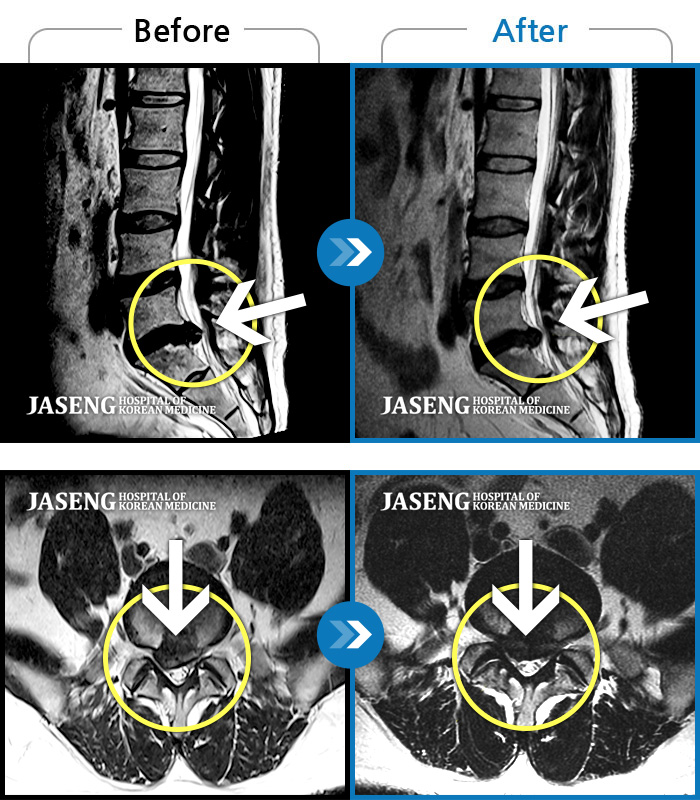

ȯںп Ǹ ǿ ԿǾ, ο ġ ۿ Ƿ ġḦ Ͻñ ٶϴ.